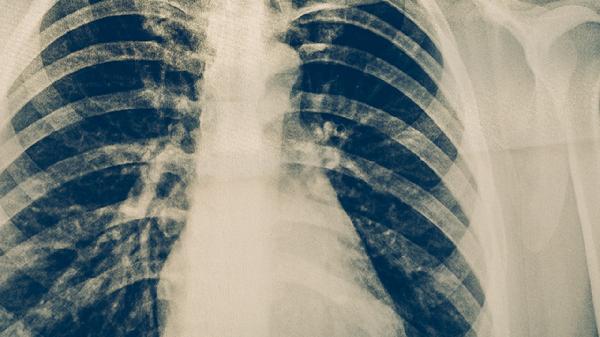

肺癌患者出现咳嗽症状可遵医嘱使用复方甘草片、氢溴酸右美沙芬口服溶液、磷酸可待因片、盐酸氨溴索口服溶液、苏黄止咳胶囊等药物。肺癌咳嗽可能与肿瘤压迫、气道炎症、感染、胸膜受累或治疗副作用有关,需结合病因针对性用药并严格遵循医嘱。